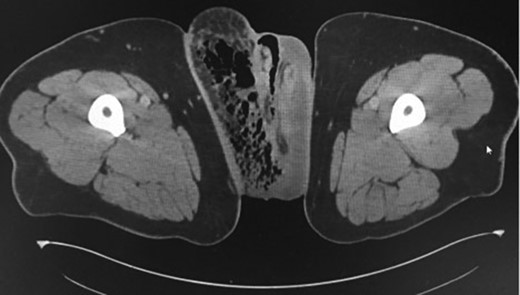

A 45-year-old male, with a background of type 2 diabetes mellitus and morbid obesity (BMI 40.9) presented septic to the Emergency Department, with a one-week history of increasing scrotal pain, penile discomfort, and difficulty ambulating. He was febrile and tachycardic on presentation. Physical examination revealed a grossly swollen and oedematous scrotum with tissue necrosis evident over the right posterior hemiscrotum. Erythema and induration extended to the rectum, pubic and right inguinal regions. Biochemistry revealed a polymorphonuclear leucocytosis, hyperglycaemia and lactic acidosis. A computed tomography scan of his abdomen/pelvis confirmed a markedly oedematous right hemiscrotum with extensive subcutaneous emphysema tracking into the right inguinal region and anterior abdominal wall (Figs 1 and 2).

Axial CT scans of pelvic region demonstrating gas in the right groin region.